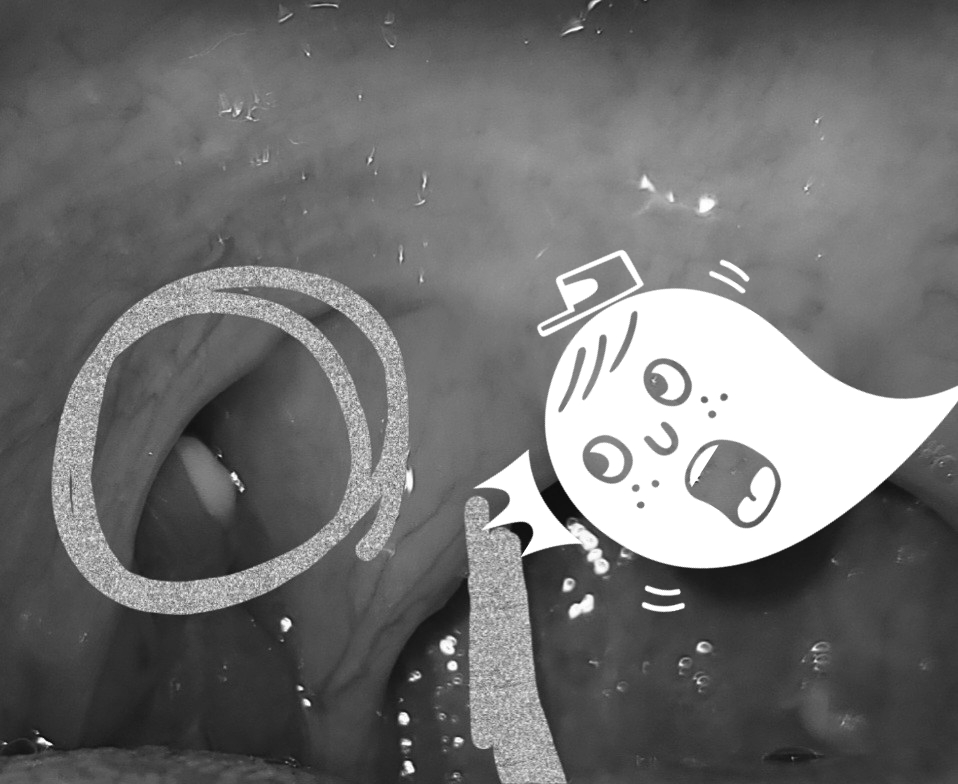

이렇게 편도결석으로 막혀있던 편도선은 찢어진것같은.. 목이 아직 부었고, 또 핸드폰 프레시를 비추어 확인해보니…..

…….?? 당신 또 뭐에요…………………………..처음에는 편도결석제거하고 식사가능하다고 해서 점심때 먹은 밥알인가 싶어서 계속 양치질하고 양치질도 하고 치간칫솔로 찔러도 봤는데 나오지 않는걸 보니……당신은 안에 숨어있는 편도결석이구나!!!!!!!!!!!!♪누군가가 이제야 불쑥 나와 ㅠ_ㅠ……여러 편도결석제거 영상을 보면 제거한 장소 안에 숨어있던 편도결석이 꽤 출몰하는 사례도 있었어..